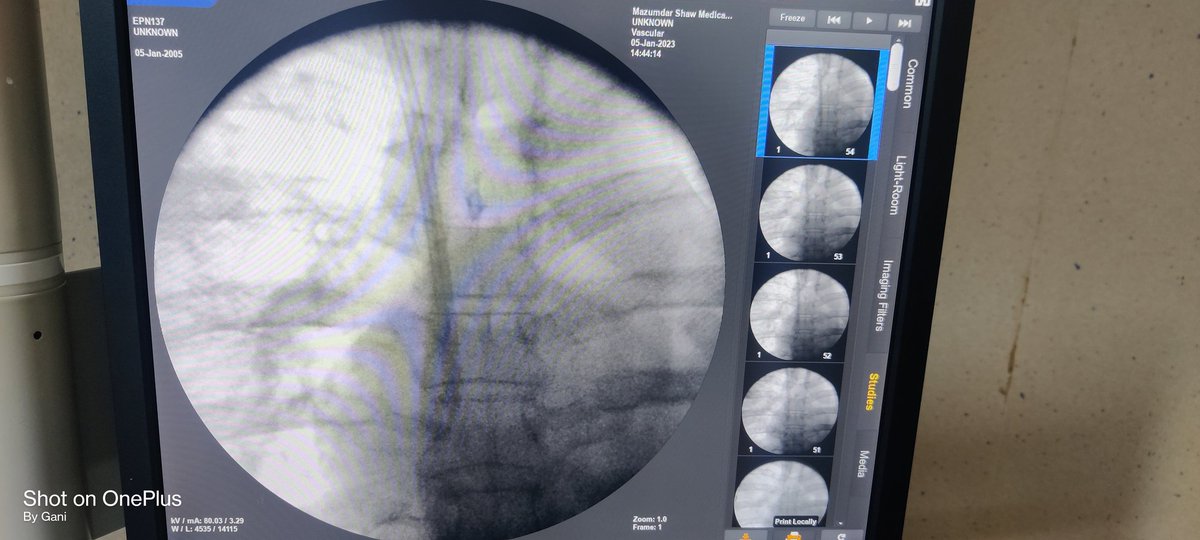

#micropuncture kit is such a boon for patients with thrombosed IJV Pic : 1 not able to pass the guidewire due to thrombus Pic 2: guidewire has gone after puncturing the thrombus with micropuncture guidewire Pic 3: final outcome @AVATAROrg @prashantnephro @fearingforties

Pic : 1 not able to pass the guidewire due to thrombus

Pic 2:  guidewire has gone after puncturing the thrombus with micropuncture guidewire

Pic 3: final outcome